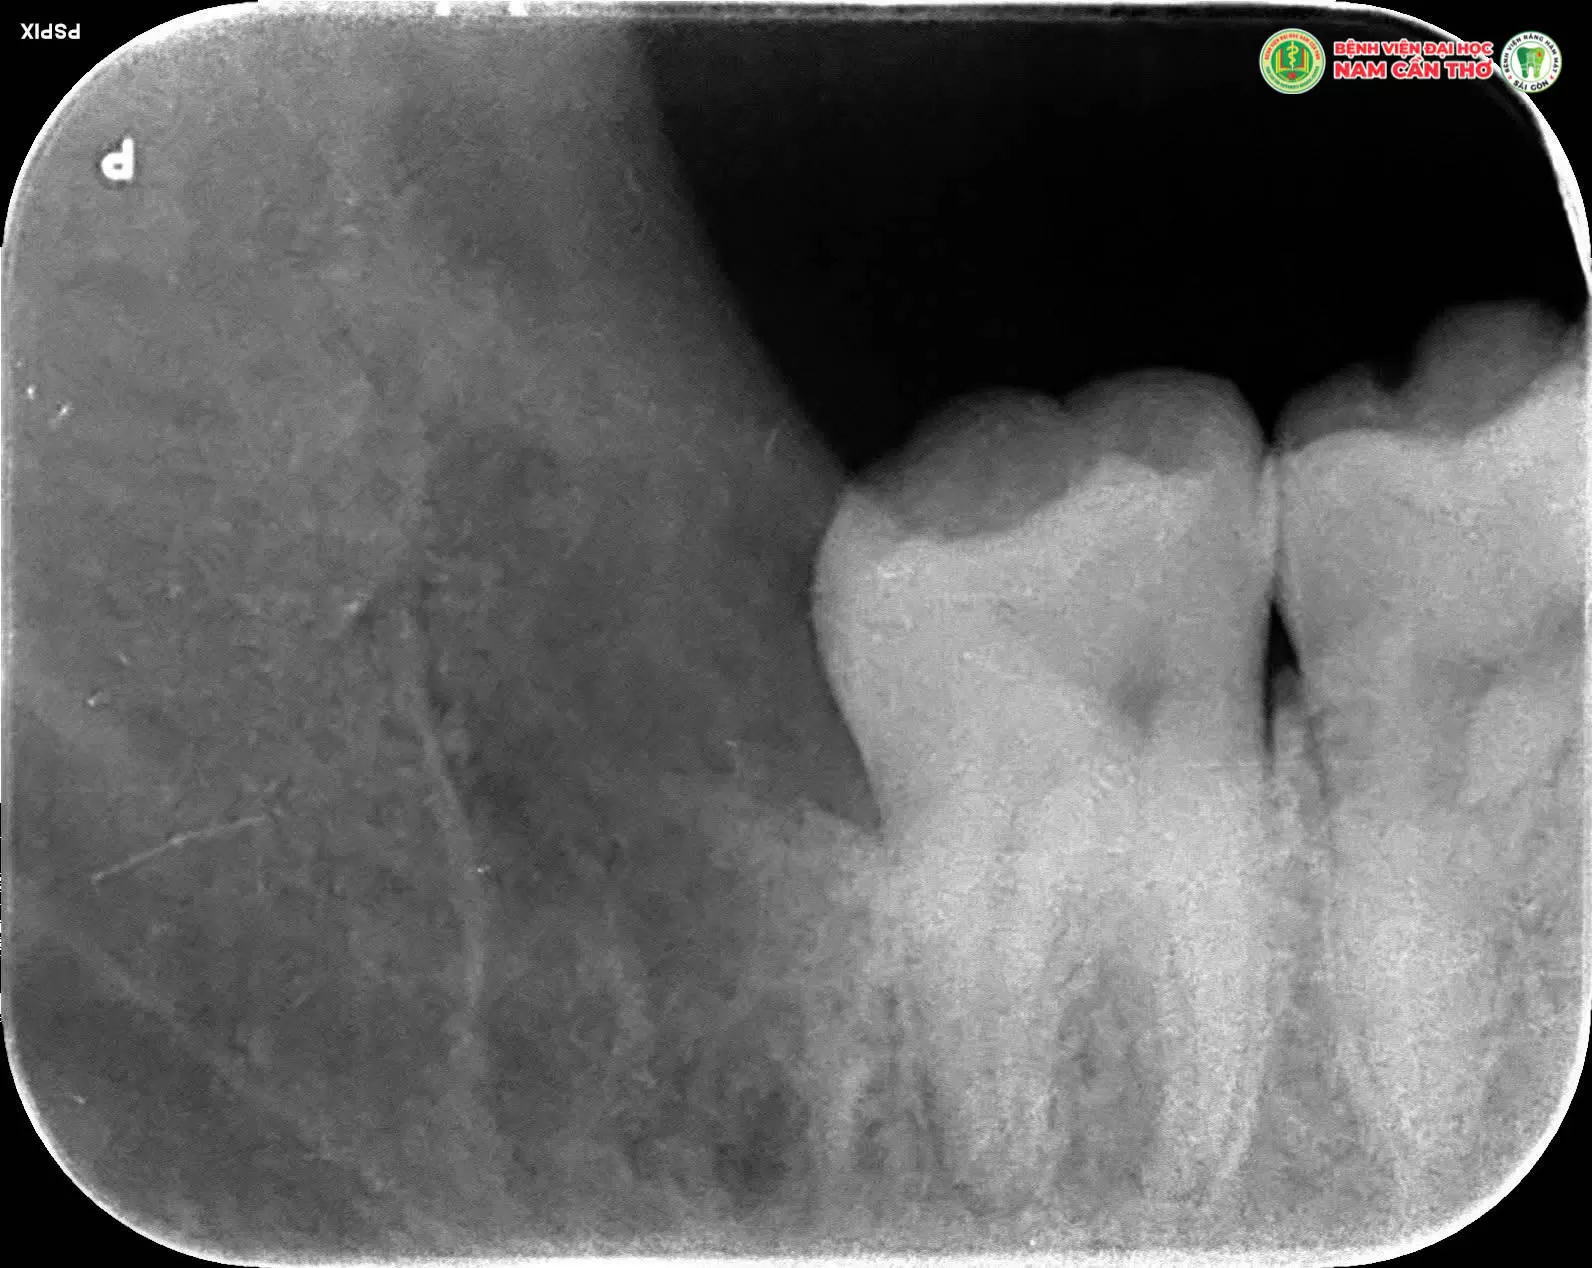

✨Răng khôn thường mọc lệch, mọc ngầm hoặc chen chúc gây đau nhức viêm nhiễm và ảnh hưởng đến các răng bên cạnh. Việc nhổ răng khôn đúng thời điểm đúng kỹ thuật là cần thiết để đảm bảo sức khỏe răng miệng lâu dài.